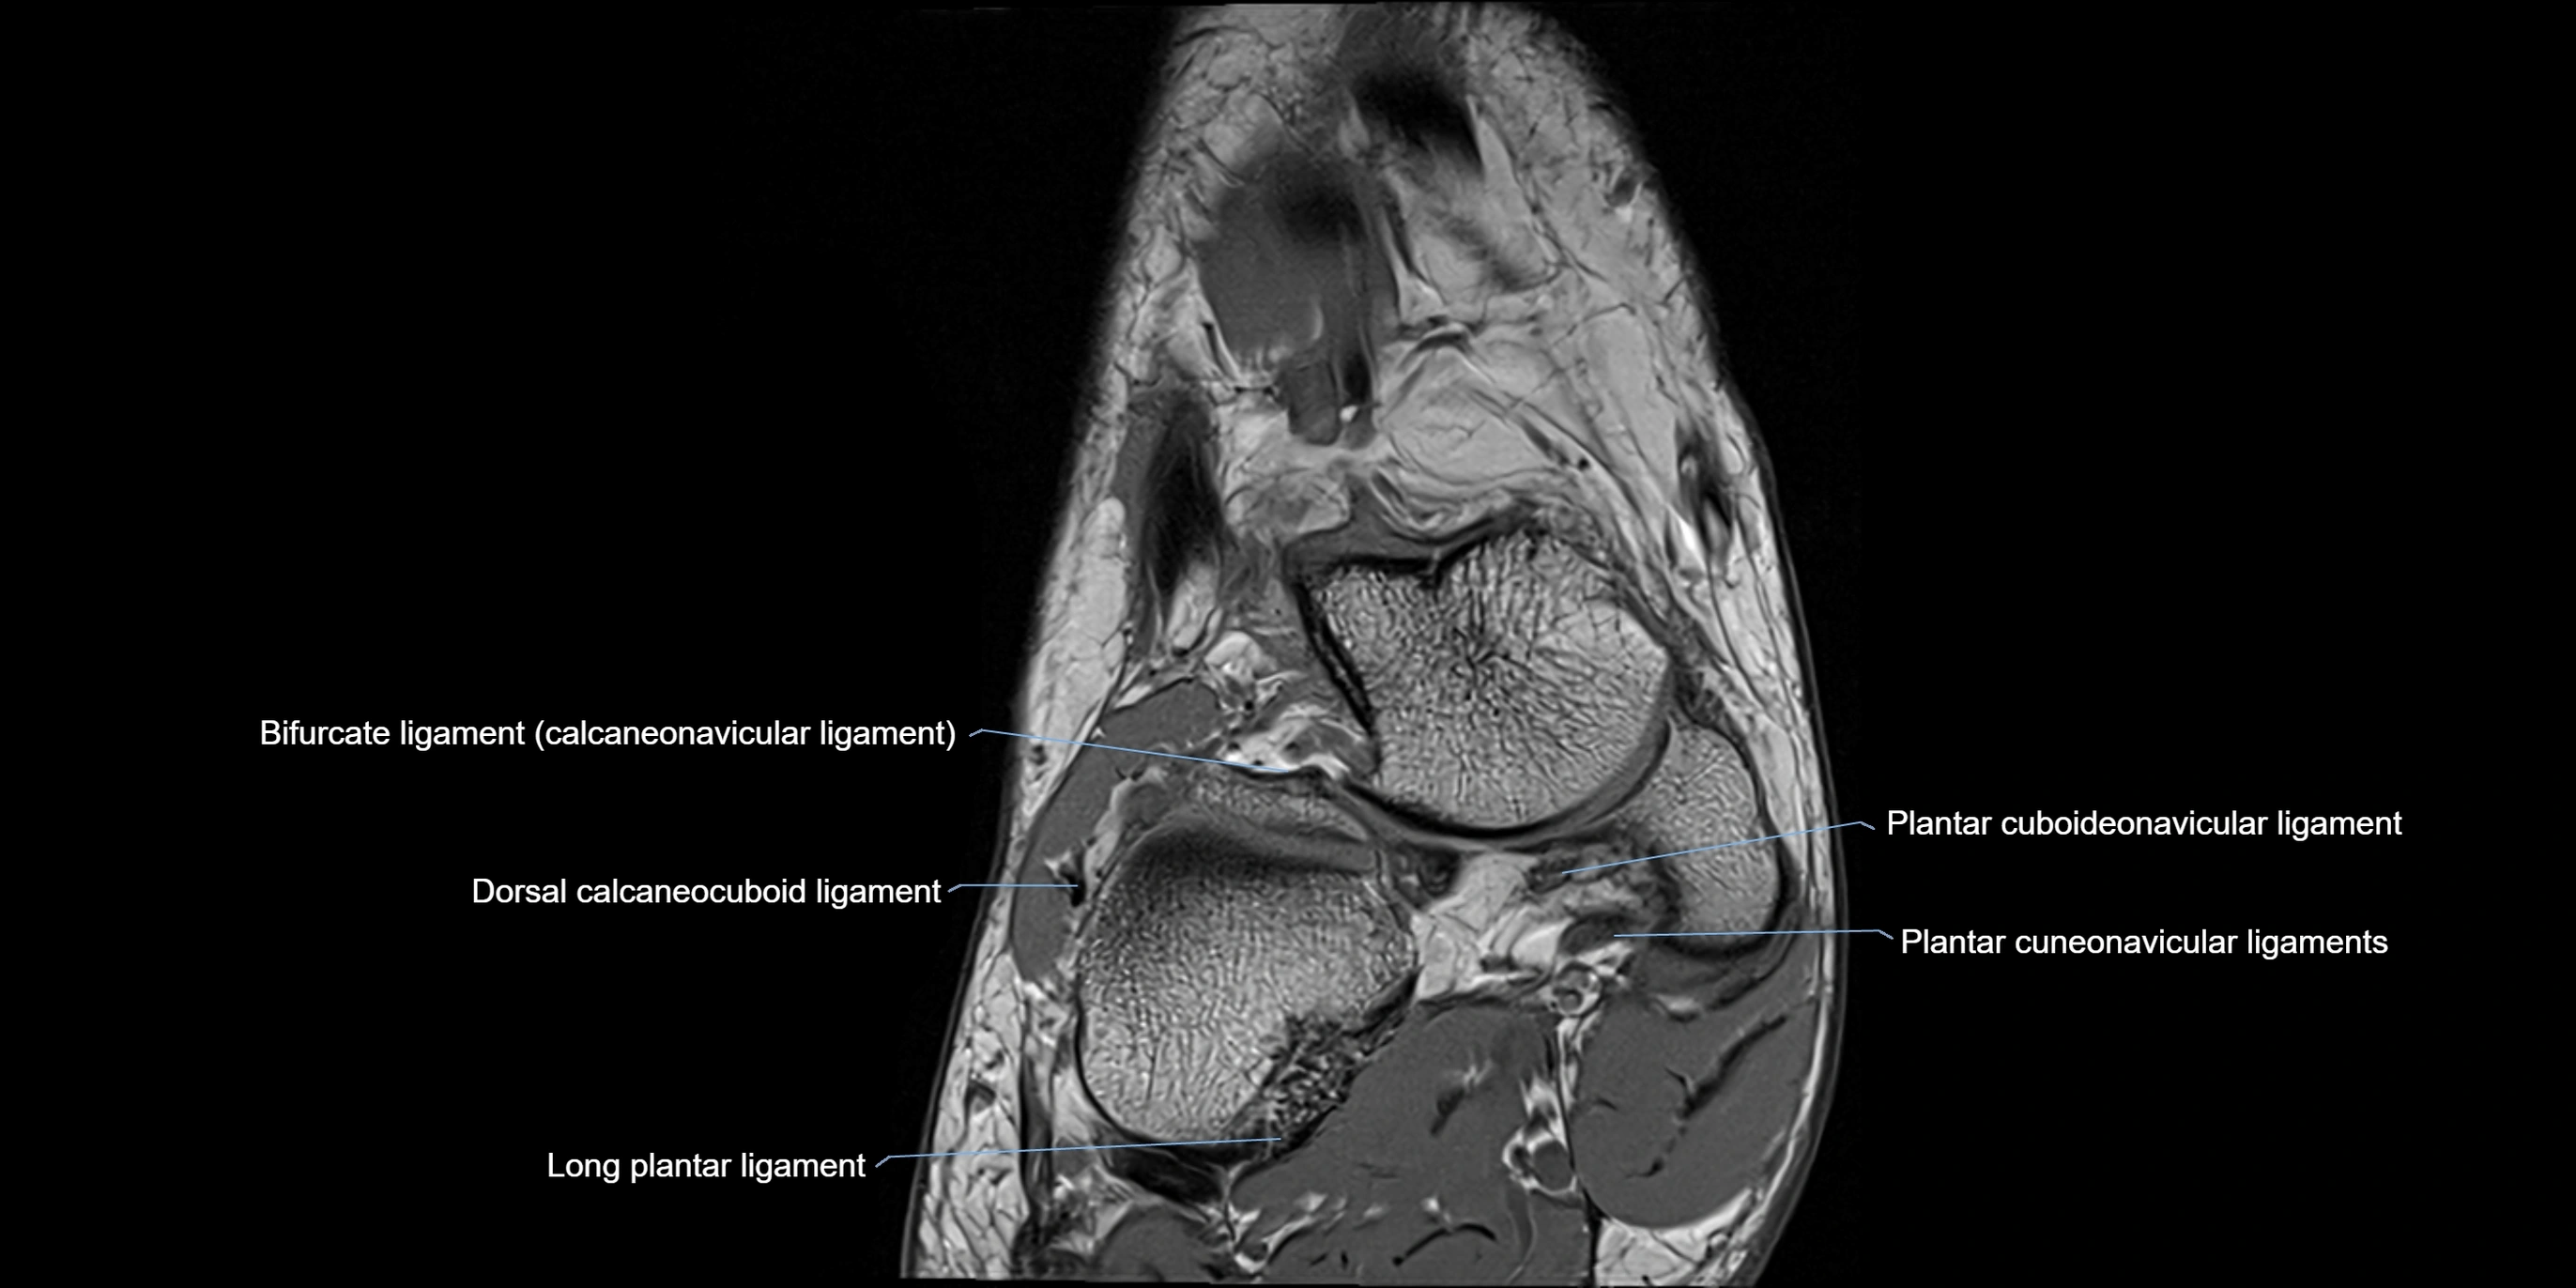

MRI image

image